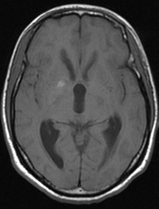

A 26-year-old man was admitted in our Rehabilitation Unit in May 2022 after being diagnosed with TBM. The patient presented to the emergency department with a 2-week history of fever, disorientation, decreased lower limbs strength and urinary incontinence. He had a recent history of contact with tuberculosis (TB), with a positive interferon gamma release assay test. Brain magnetic resonance imaging (MRI) with gadolinium contrast revealed hydrocephalus and diffuse leptomeningeal enhancement with basal cistern involvement (Figure 1). Acute ischemic brain lesions with hemorrhagic transformation in the right globus pallidus and anterior limb of internal capsule consistent with infarctions due to infectious arteritis, were also noted (Figures 2 & 3). Spine MRI with gadolinium contrast revealed diffuse cervical, thoracic, lumbar and sacral enhancement of meninges overlying the spinal cord and cauda equina nerve roots (Figure 4). These images were suggestive of TB infection. Blood cultures, serologies and cerebrospinal fluid (CSF) culture were negative for TB bacilli and he had no relevant medical history, including risk factors for being immunocompromised. Nevertheless, presumptive diagnosis of TBM was made in the setting of relevant clinical and epidemiologic factors in combination with typical CSF and MRI findings.

Figure 2 Brain MRI T1 images, axial view.